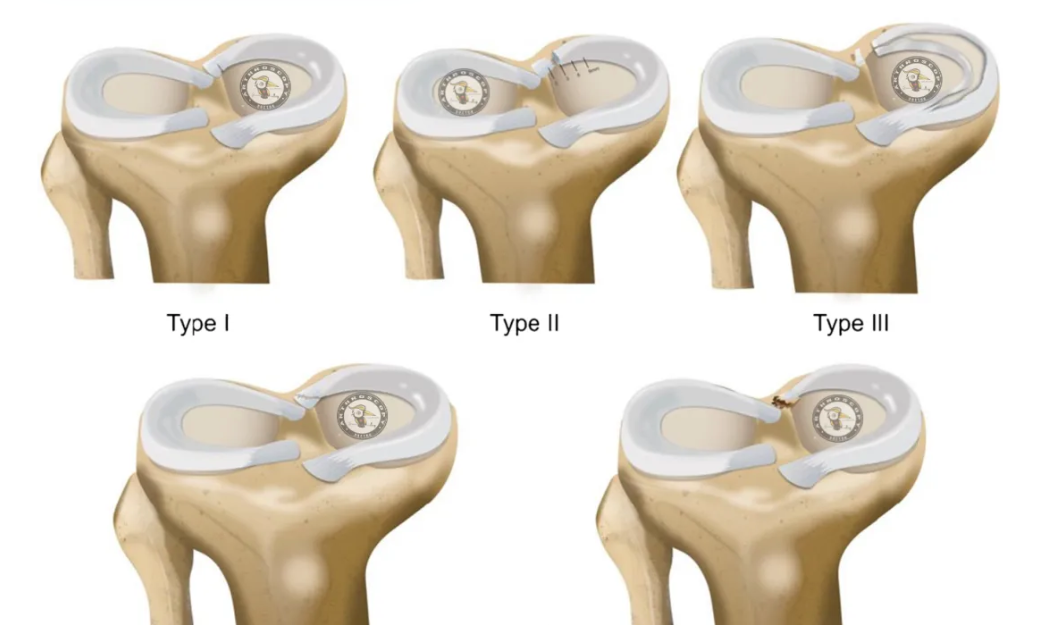

人工膝关节置换基本技术